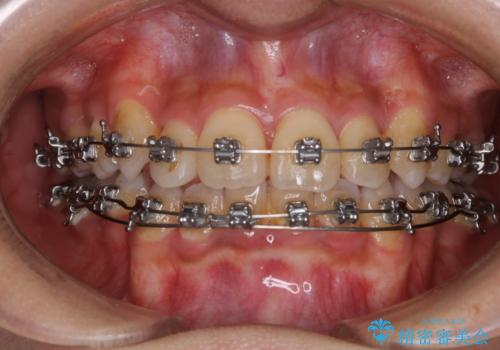

インビザラインによるガタつきの治療 クロスバイトの改善

- 矯正装置

- invisalign Full

- 治療期間

- 1年